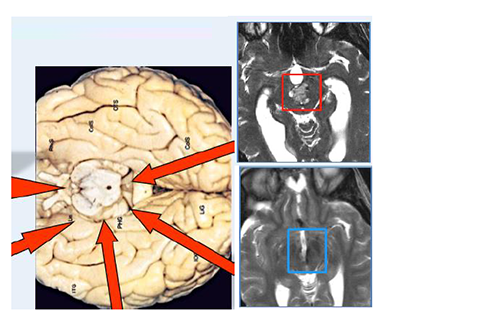

一名有高血压史的62岁女性由于意识突然紊乱而被送往另一家医院。CT扫描显示存在原发脑桥出血。她接受了2周的保守治疗。然而,她的症状没有好转,她被转到德国INI医院。入院时,她表现出意识障碍(GCS评分,13),左侧偏瘫(MMT评分,3),右侧神经III麻痹,左侧面神经(神经VII)麻痹(HB级2)。发病后21天,她通过半枕外侧入路进行手术。患者的意识水平,运动功能,眼球运动和面神经麻痹在术后早期开始好转。术后MRI显示完全切除脑桥血肿。她恢复后神志清,并且独自步行出院。

由于突然意识丧失和构音障碍,一名71岁男子被送往德国INI治疗。入院时,他表现出意识障碍(GCS评分,13),右侧偏瘫(MMT评分,3),左侧神经III和神经VI麻痹,左侧VII麻痹(HB级2)。CT扫描显示存在原发脑桥出血(下图,左起二个)。在发病后6天,在家人提供书面知情同意书后,他通过跨半长位置的半长方位进行手术。血管通过菱形窝从面部三角区撤离.尽管他的眼球运动仍然受损,但他的意识水平,运动功能和面部麻痹在术后早期开始好转。术后MRI显示完全切除脑桥血肿。